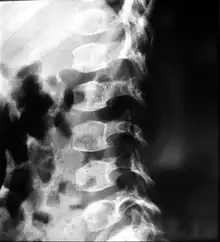

| A: A 6 1/2-year-old male with spondyloepiphyseal dysplasia congenita. Short stature, disproportionately short trunk, and kyphoscoliosis. B: Preoperative and postoperative X-ray | |